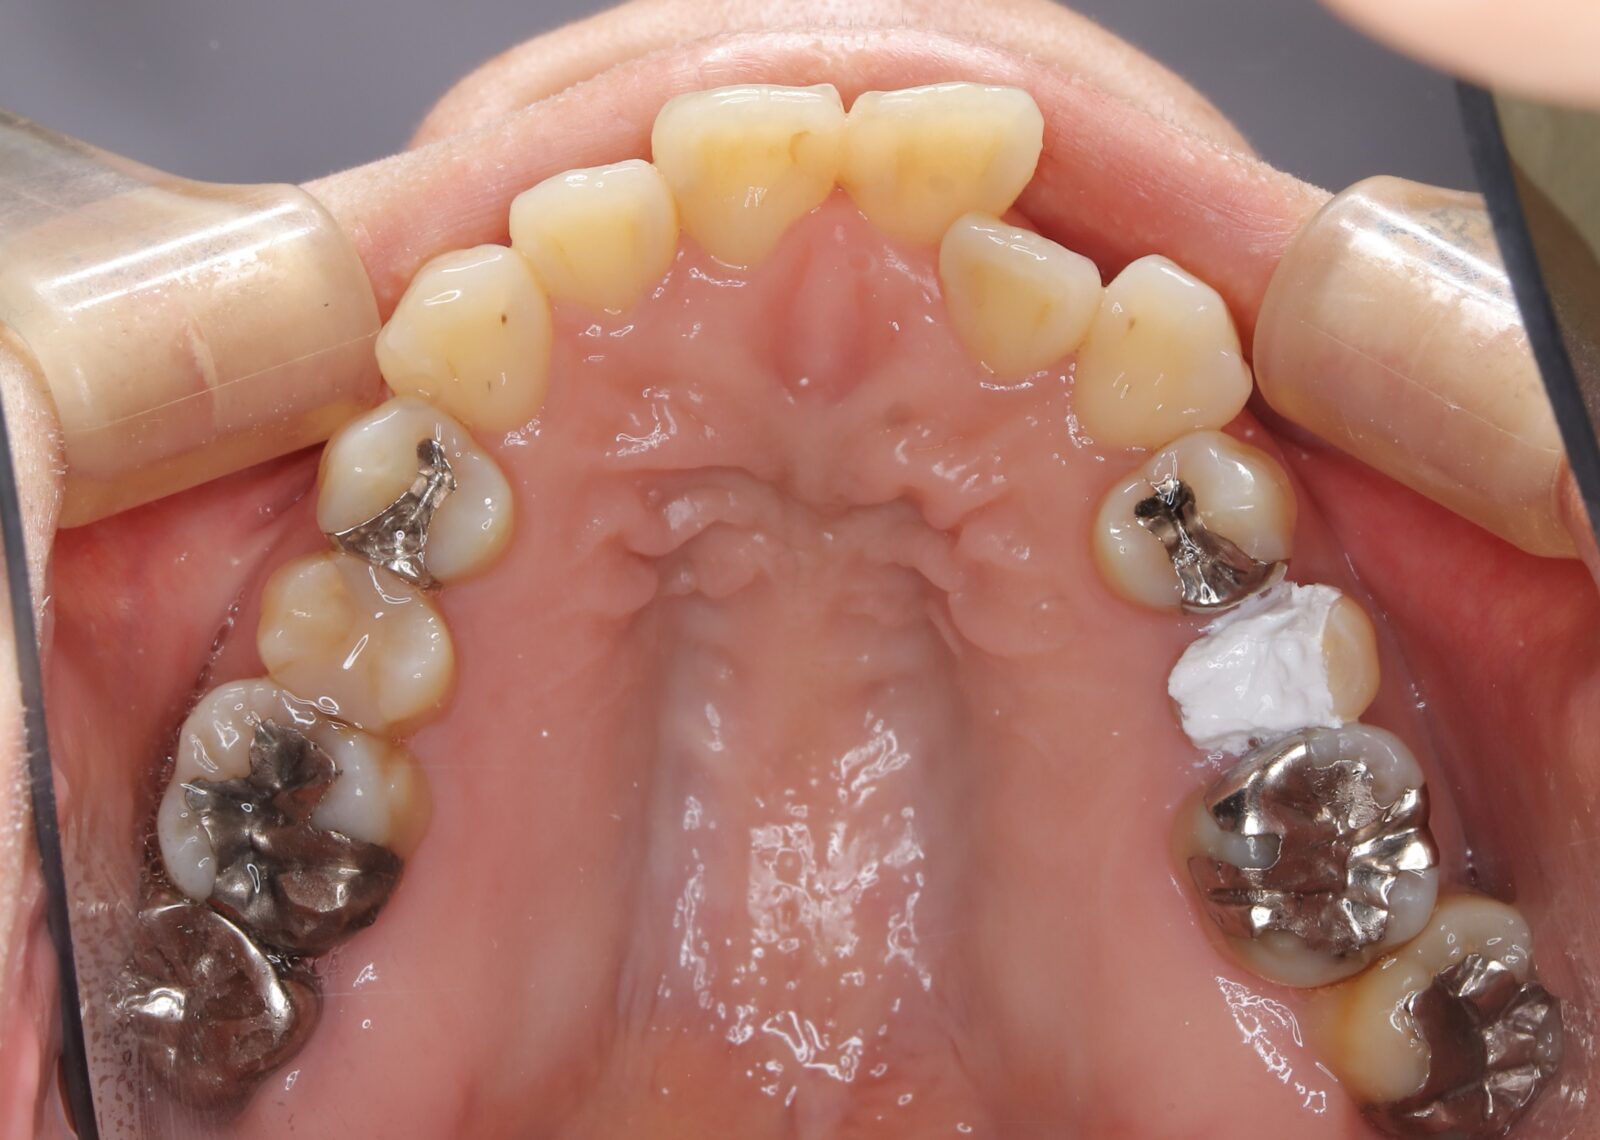

矯正と補綴が必要で実施した症例

左側に隙間。歯の数が少ない。もともと2番と7番がない。(先天欠如)歯の数が少ないため上顎のアーチ全体が小さい。歯槽骨の幅も狭く、歯肉も薄い。骨質も弱かった。

上顎左右2番と6番が先天欠如。下顎左右1番も先天欠如でもともとブリッジが装着されていた。

左右非対称なすきっ歯。上顎の前歯がないので左側の隙間を左右2番相当部に集めた。

上下の前歯が反対の噛み合わせ(受け口)で、干渉しているためうまく閉じることができず、奥歯は左右同時に噛めないので、どこかにずらさないと口を閉じられない。

左右の歯を同時に合わせることができず、どこで噛んだら良いかわからない噛み合わせでした。

小臼歯部は噛み合うことがない側方の開口状態。矯正と補綴が必要なケース。 主訴は顎の不調と歯軋り、夜間の食いしばり。

マルチブラケットとインビザラインを併用し、クラウンとブリッジを装着しました。

上顎左右2番は、歯が入るスペースを作り、ブリッジを装着しました。

他の歯医者で何軒も断られていました。 骨の幅がうすくインプラントはできない。骨の質も柔らかい。PCR検査の結果も歯周病ハイリスク患者でした。

歯の位置は、本人の顎が安定する場所を探して着地した。 左右で噛み合わせが非対称で、理想的な歯のポジションを獲得できなかったものの、左右同時に噛むことができるようになった。

顎関節の症状も落ち着いて、開口障害や、顎の痛みは無くなった。

矯正治療はどの装置を選択しても歯周病のリスクを高めてしまう。

これ以上の歯の移動が歯周病と骨質、骨の代謝のバランスの兼ね合いで困難であると判断し、ここが着地点とした。